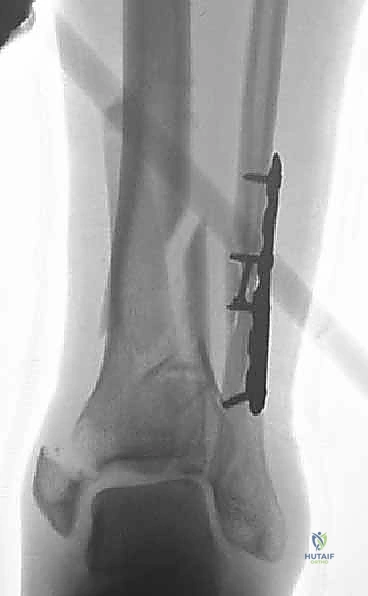

العلاج الجراحي: التثبيت الداخلي المفتوح (ORIF) - المعيار الذهبي

بالنسبة لجميع كسور البيلون المنزاحة والمفتتة، يعتبر التثبيت الداخلي المفتوح (Open Reduction and Internal Fixation - ORIF) هو العلاج القياسي والمعيار الذهبي.

في صنعاء، يطبق الأستاذ الدكتور محمد هطيف المبادئ الأربعة الكلاسيكية التي وضعها (Ruëdi and Allgöwer) والتي تم تحديثها بالتقنيات الحديثة، وتتمثل أهدافها في:

1. إعادة بناء مفصلية دقيقة (Anatomic Articular Reduction): لا مجال للخطأ هنا. يجب إعادة بناء السطح المفصلي بدقة المليمتر لتجنب احتكاك الغضاريف وحدوث خشونة مبكرة.

2. استعادة طول الطرف ومحاذاته (Restoration of Length and Alignment): لمنع العرج وتوزيع الوزن بشكل غير متساوٍ على الركبة والورك.

3. التطعيم العظمي (Bone Grafting): لملء الفراغات الناتجة عن انضغاط العظم الإسفنجي.

4. تثبيت الكسر المستقر (Stable Fixation): باستخدام شرائح ومسامير متطورة للسماح بالحركة المبكرة للمفصل.